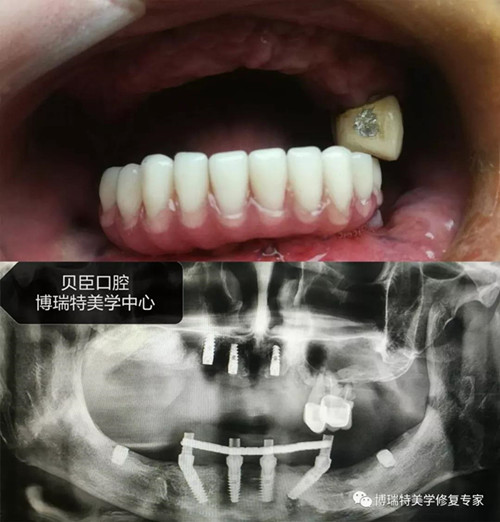

病例展示

案例一

案例二